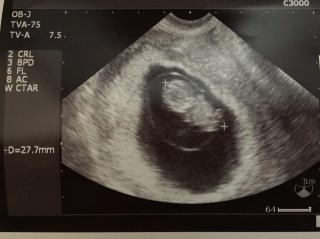

7週で心拍確認できていましたが、胎芽7ミリと小さめで心配でしたが、2週間で2センチも大きくなってくれていました!CRL27.7センチで順調とのことです。ここ最近つわりも軽くなって不安でしたが、つわりと赤ちゃんの成長は関係ない!と実感しました。